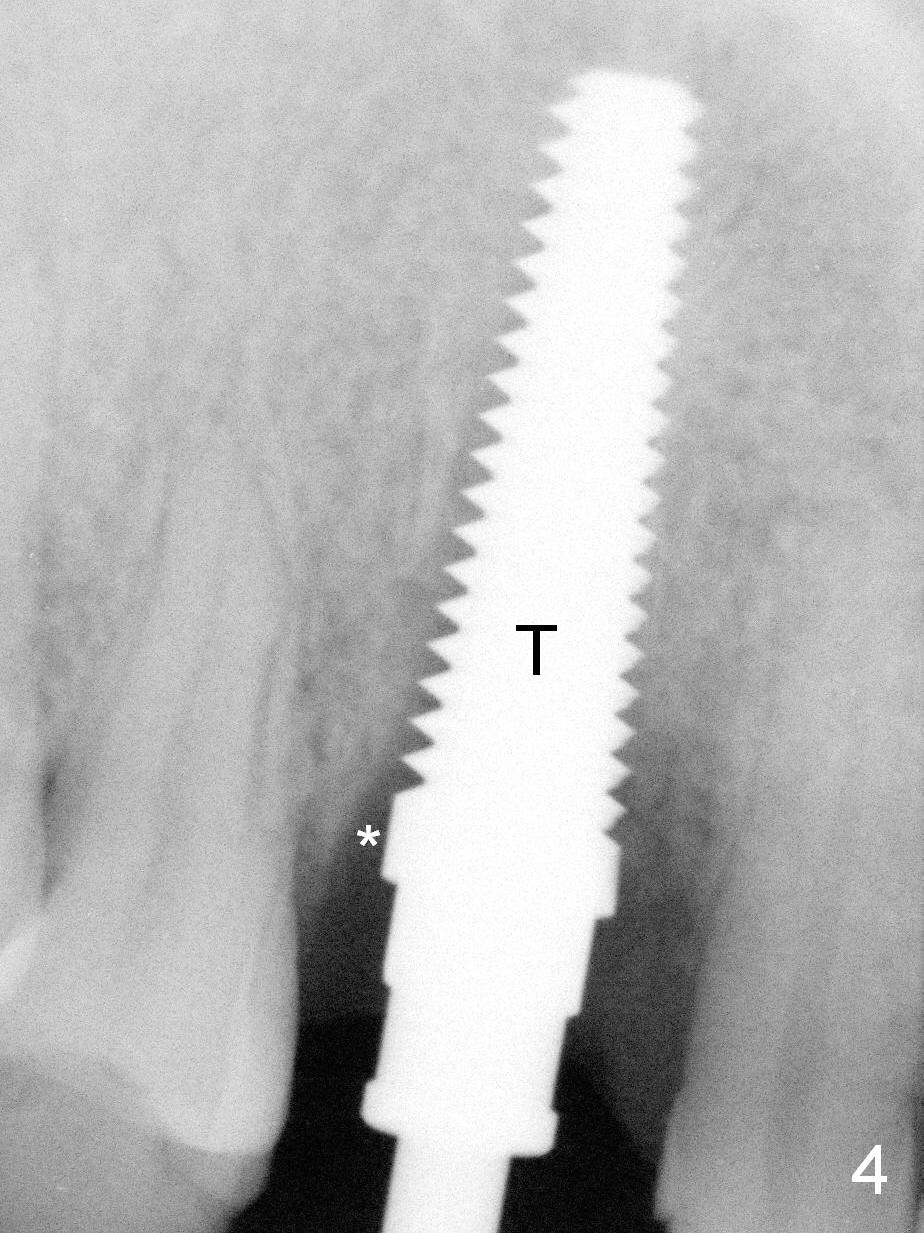

Lengthwise, a longer osteotomy is needed (Fig.4): 20 mm at the gingival level, 17 mm at the bone level. Distal to the 5 mm tap (T) is a gap (*).